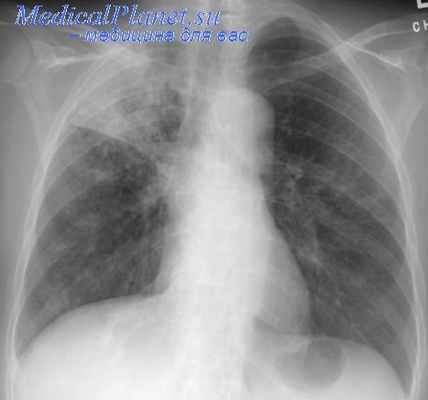

Полный клинический эффект мы расценивали при ликвидации каверны и отсутствия М. Т. в мокроте, такой результат был получен в 96,0% в I группе больных и в 91,2% во II гр. б-х. Выздоровление после дополнительных операций, произведенных по поводу осложнений (удаление сгустков крови, ререзекции, торакопластики) в 1,5% в I группе и в 1,4% во второй.

Выписались без эффекта с остаточной плевральной полостью и реактивацией процесса 0,7% в I группе и 3,7% во II. Наступил летальный исход в 1,8% в I группе и в 3,7% во II Общий процент эффективности сохраняется высоким 96— 91,2%. Значительный процент послеоперационных осложнений во II группе, способствующий прогрессированию процесса, объяснялся как тяжестью больных, так и травматичностыо операций.

Основной причиной летальных исходов во II группе являлась легочно-сердечная недостаточность, как следствие длительного и распространенного фиброзно-кавернозного тбк легких.

В отдаленном периоде после выписки от 2 до 5 лет отмечалось снижение результатов хирургического лечения за счет летальных исходов в связи с прогрессированием туберкулеза, а также от других причин, не связанных с основным процессом (рак желудка, алкоголизм, болезни крови, болезни центральной нервной системы, травма и др.). Однако, общий процент благоприятных исходов оставался высоким 95,0 в I группе и 93,3% во II.При благоприятном послеоперационном периоде больные выписывались через 1—1,5 месяца после операции на санаторно-курортное лечение, продолжительностью 2 месяца, с последующим наблюдением диспансера.

Через 6 месяцев после частичных резекций легкого восстанавливались функциональные резервы и больные возвращались к труду.

После обширных резекций и пульмонэктомии при неполном восстановлении функциональных резервов больные получали инвалидность с частичным восстановлением трудоспособности.Таким образом, хирургический метод оправдан длительным наблюдением за диспансерными контингентами.